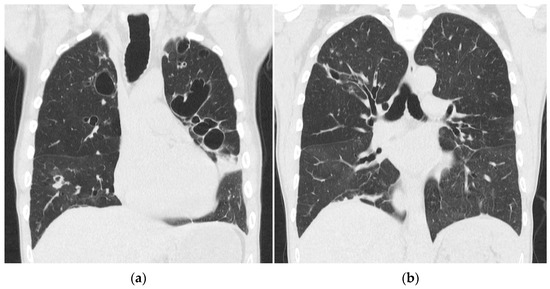

After 13 weeks of hospitalization in total, he was discharged with home oxygen therapy and offered rehabilitation. Five months later, he did not need home oxygen therapy but was still limited in his daily life because of troubled and wheezing breathing. A spirometry showed severely reduced lung capacity with a forced vital capacity (FVC) of 2.56 L (51.5% of the expected capacity) and signs of emphysema and obstruction. A CT scan of the chest showed bilateral pulmonal cysts, bronchiectasis, consolidation, and dilation of the trachea (Figure 3). Scanning in the expiratory phase showed an almost complete collapse of the trachea and comprehensive air trapping, and he was diagnosed with tracheomalacia. Now, 4 years later, the patient is still followed in the Pulmonology Out-Patient Clinic at the National Hospital of the Faroe Islands. One and a half years after discharge, he was examined at a German thorax clinic to find out if he could benefit from a tracheal stent implantation, but an indication was not found. He now receives intermittent continuous positive airway therapy (CPAP), regular pneumococci, influenza vaccinations, and prophylactic antibiotics.

Figure 3. (a,b) CT scan of the chest with coronal reconstruction, showing bilateral pulmonal cysts, bronchiectasis, consolidation and dilation of the trachea, 5 months after admission.